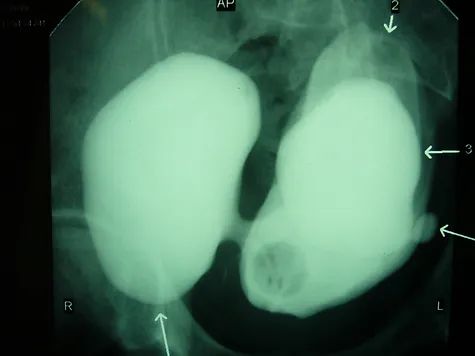

A hormone-secreting tumour that can occur in the adrenal glands. Phaeochromocytomas usually develop in the small glands on top of the kidneys (adrenal glands). They most commonly affect people between the ages of 20 and 50, but can occur at any age. Because of hormones secreted, symptoms include high blood pressure, sweating, rapid heartbeat and headache. Surgery to remove the tumour is usually required.